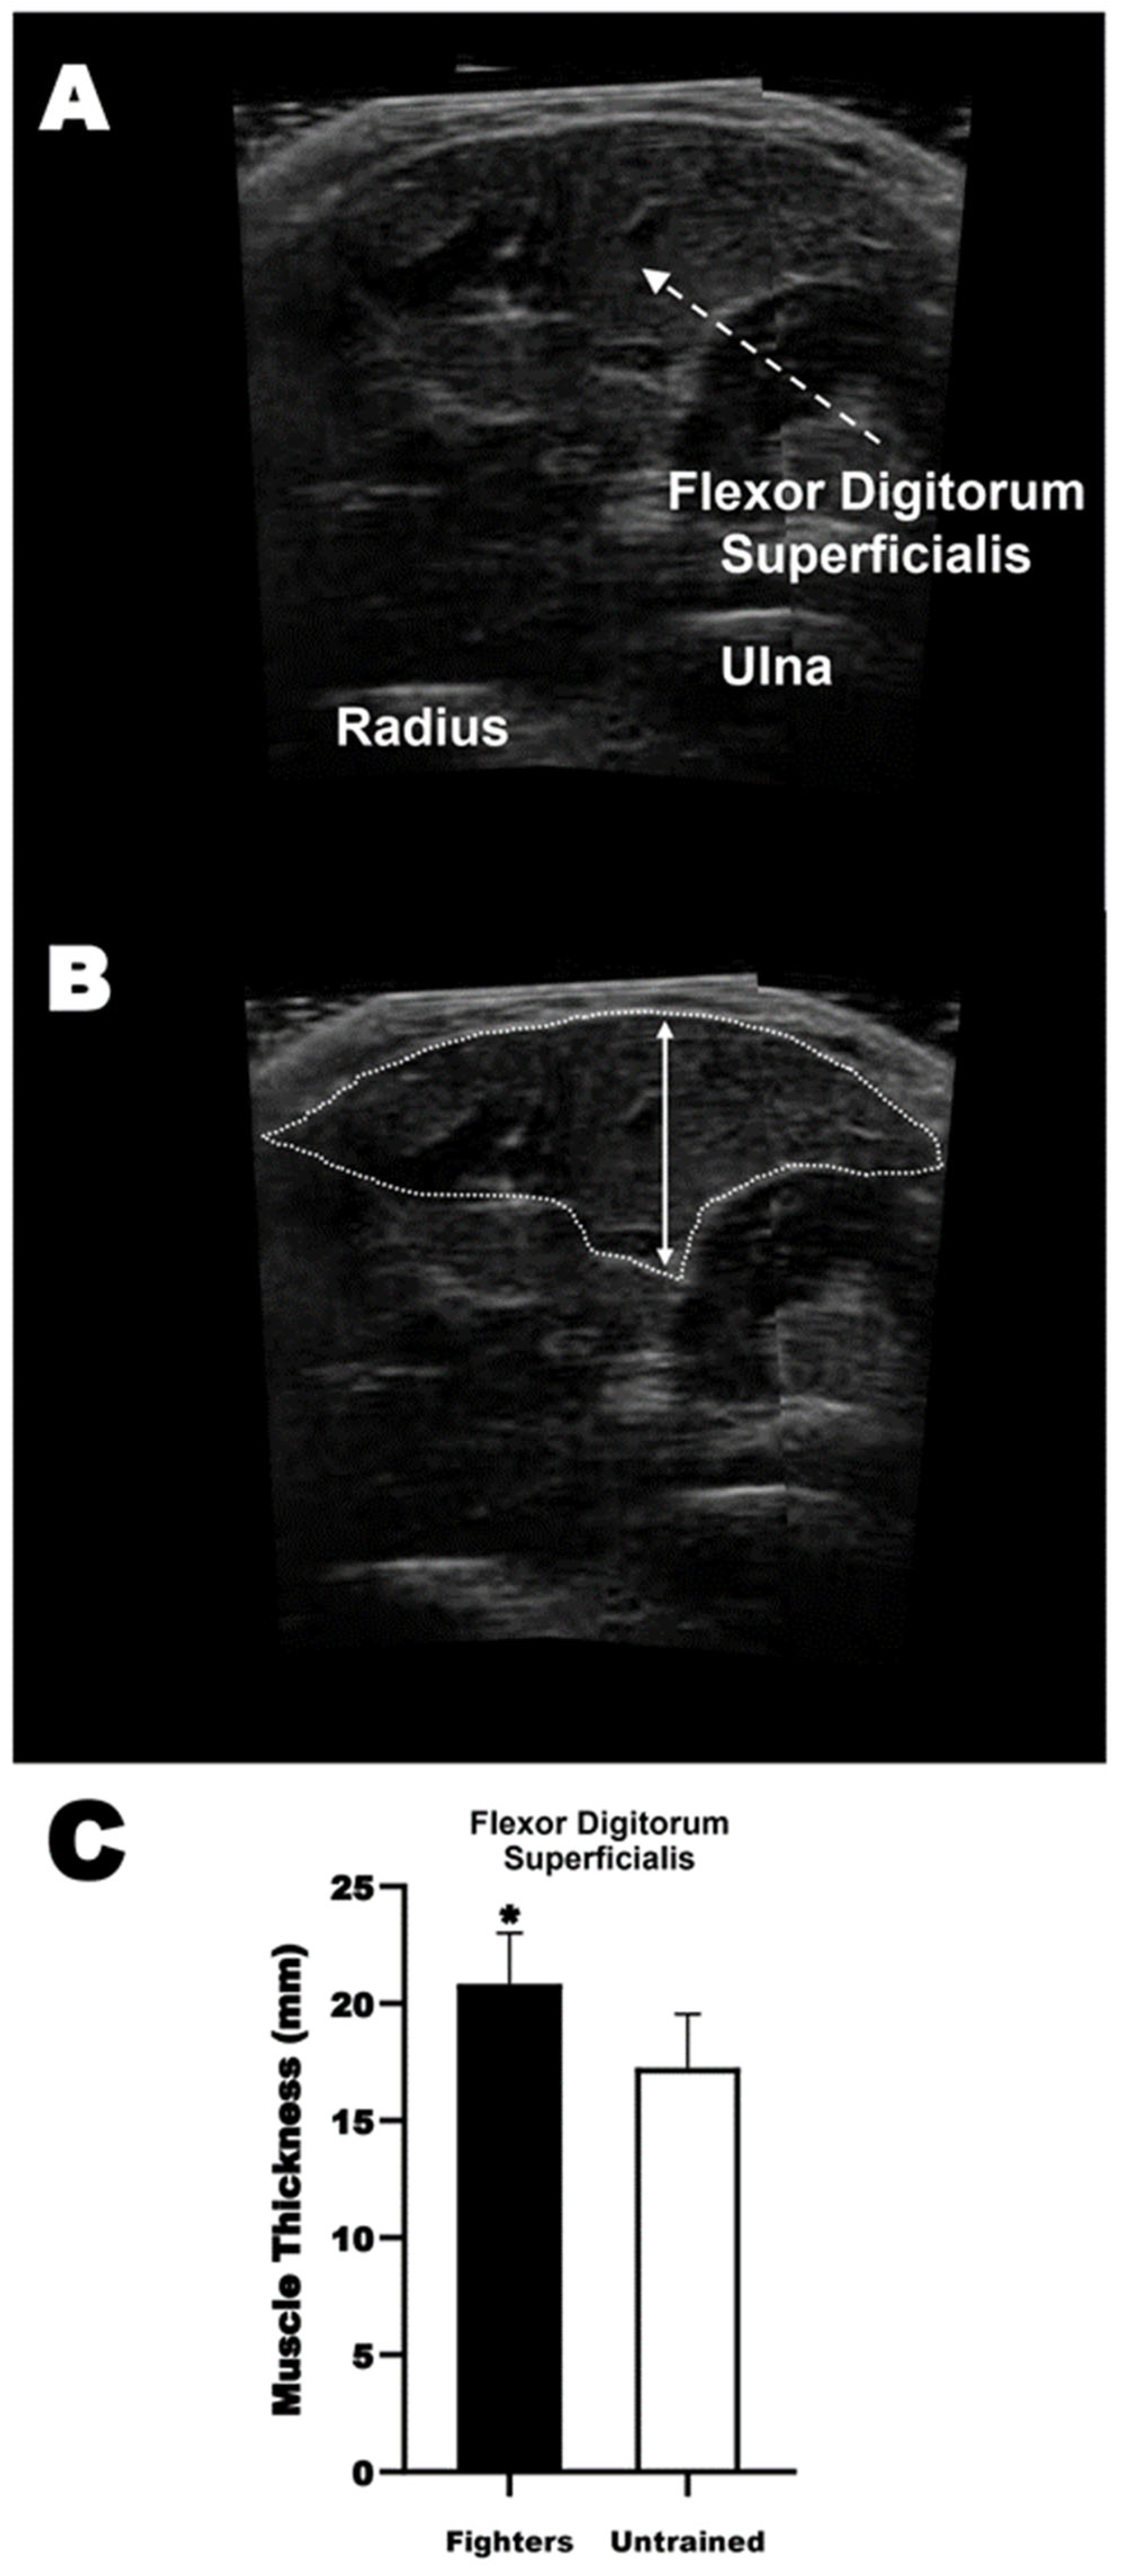

2.9. Ultrasonography